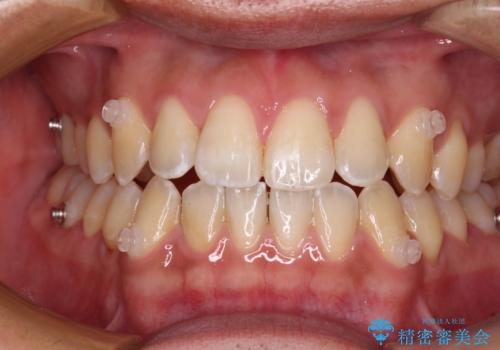

ワイヤー矯正を併用したインビザライン矯正治療

- 前歯のデコボコを気にして来院された患者様です。

歯列としてはワイヤー装置でもインビザラインでも対応可能でしたが、インビザラインが苦手とする上顎側切歯(真ん中から2番目の歯)の舌側転位が顕著でした。

治療の確実性を上げるために、インビザライン開始前に上顎のワイヤー装置にて舌側転位を解消し、その後インビザラインにて矯正治療を行うこととしました。

前歯のデコボコが早めに改善され、スムーズに治療を終えることができました。